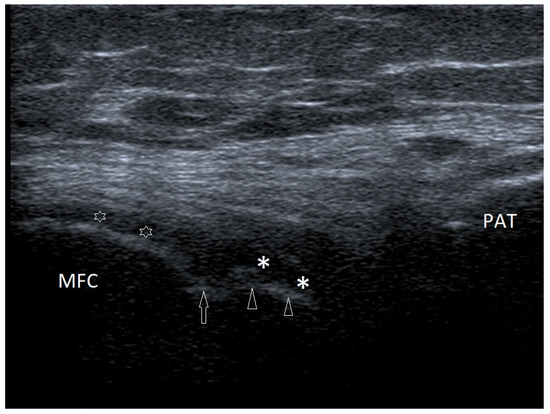

Basic Differences and Most Common Findings in Ultrasound Examinations of Musculoskeletal System in Children: A Narrative Literature Review

by Tomasz Poboży, Wojciech Konarski, Karolina Piotrowska-Lis, Julia Domańska, Kamil Poboży and Maciej Kielar

We present basic differences in the musculoskeletal ultrasound examinations between adults and children. Examiners who deal with adults on a daily basis have shared concerns about examining children. Such concerns may arise from the different approach to child ultrasounds, but they also come [...] Read more.

We present basic differences in the musculoskeletal ultrasound examinations between adults and children. Examiners who deal with adults on a daily basis have shared concerns about examining children. Such concerns may arise from the different approach to child ultrasounds, but they also come from differences in anatomical characteristics according to developmental age. We discuss the presence of growth plates, as well as non-mineralized parts of the bones. We also refer to the pathologies most often found in ultrasounds in early developmental stages. In the PubMed database, the set of keywords: “msk ultrasound in children”, “pediatric msk sonoanatomy”, “coxitis fugax”, “pediatric Baker’s cyst”, “Baker’s cyst ultrasonography”, “bone septic necrosis in ultrasonography”, “ultrasonography in juvenile idiopathic arthritis”, and “ultrasonography in juvenile spondyloarthropathies”, was used to identify a total of 1657 results, from which 54 was selected to be included in the article. We discuss the problem of osteochondritis dissecans, Osgood-Schlatter disease, examples of ligament injuries (especially in relation to the knee and ankle joints), exfoliation of growth cartilages, osteochondroma, exudates and inflammations affecting joints, and Baker’s cysts. In this way, we have collected useful information about the most common diseases of the musculoskeletal system in children. Full article

Show Figures

Figure 1